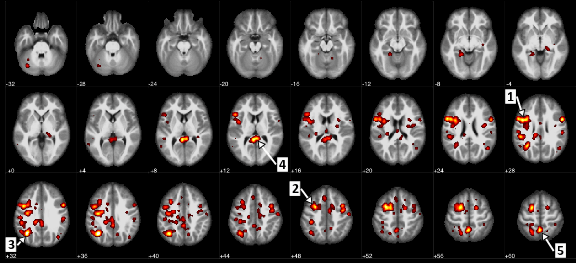

Régions du cerveau présentant une différence statistiquement significative entre les patients atteints de schizophrénie et ceux qui ne le sont pas. (La flèche 1 identifie le gyrus précentral, ou le cortex moteur, et la flèche 5 marque le précunéus, qui implique le traitement des informations visuelles).

Dans cet article, les chercheurs ont analysé des données d'imagerie par résonance magnétique fonctionnelle (IRMf) dépersonnalisées provenant de l'ensemble de données ouvertes, Réseau de recherche en informatique biomédicale fonctionnelle (fBIRN) pour des patients atteints de schizophrénie et de troubles schizo-affectifs, ainsi que pour un groupe de contrôle sain. L'IRMf mesure l'activité cérébrale par le biais des variations du flux sanguin dans des zones particulières du cerveau. Plus précisément, l'ensemble de données fBIRN reflète les recherches effectuées sur les réseaux cérébraux à différents niveaux de résolution, à partir de données recueillies pendant que les participants à l'étude effectuaient un test auditif commun. En examinant les scanners de 95 participants, les chercheurs ont utilisé des techniques d'apprentissage automatique pour développer un modèle de schizophrénie qui identifie les connexions cérébrales les plus associées à la maladie.